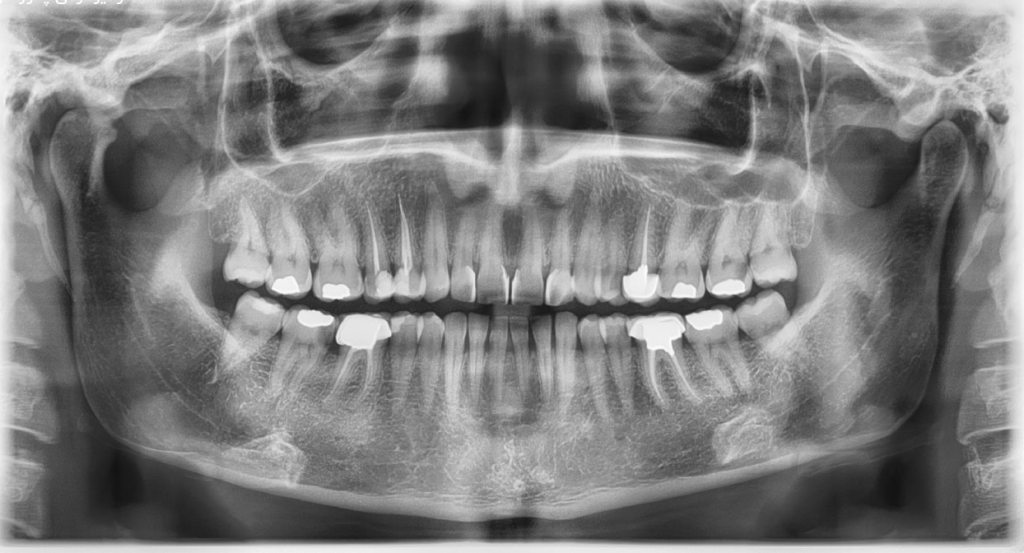

عکس OPG یک اسکن دو بعدی از قسمت تحتانی صورت است که نمای وسیع یا پانورامیکی از تمام دندانهای فک بالا و پایین بر روی یک فیلم ارائه میکند، از جمله دندانهایی که هنوز روییده یا رویش نیافتهاند، مانند دندان عقل نمای کاملی از استخوان فک و مفصل گیجگاهی فکی که فک را به بقیه قسمت های جمجمه متصل می کند، ارائه می دهد.

در این عکس از پرتوهای سطح پایین برای ایجاد تصاویری از استخوان ها و دندان ها استفاده می شود.

- مشاهده تمام دندان های بیمار و تعیین موقعیت، تعداد و رشد آنها – از جمله دندان هایی که هنوز روییده نشده اند.

- ارزیابی رشد یا تشخیص وجود دندان عقل که ممکن است نهفته باشد.

- معاینه استخوان فک.

- داشتن نمای کلی از سلامت دندان بیمار.

به عنوان مثال، نتایج عکس OPG میتواند در تشخیص پوسیدگی خاموش دندانی، از دست رفتن استخوان بین دندانها، وضعیت ریشه دندان، وجود کیست ، تومور و یا هر گونه ضایعات بدون علامت فکی موثر باشد.